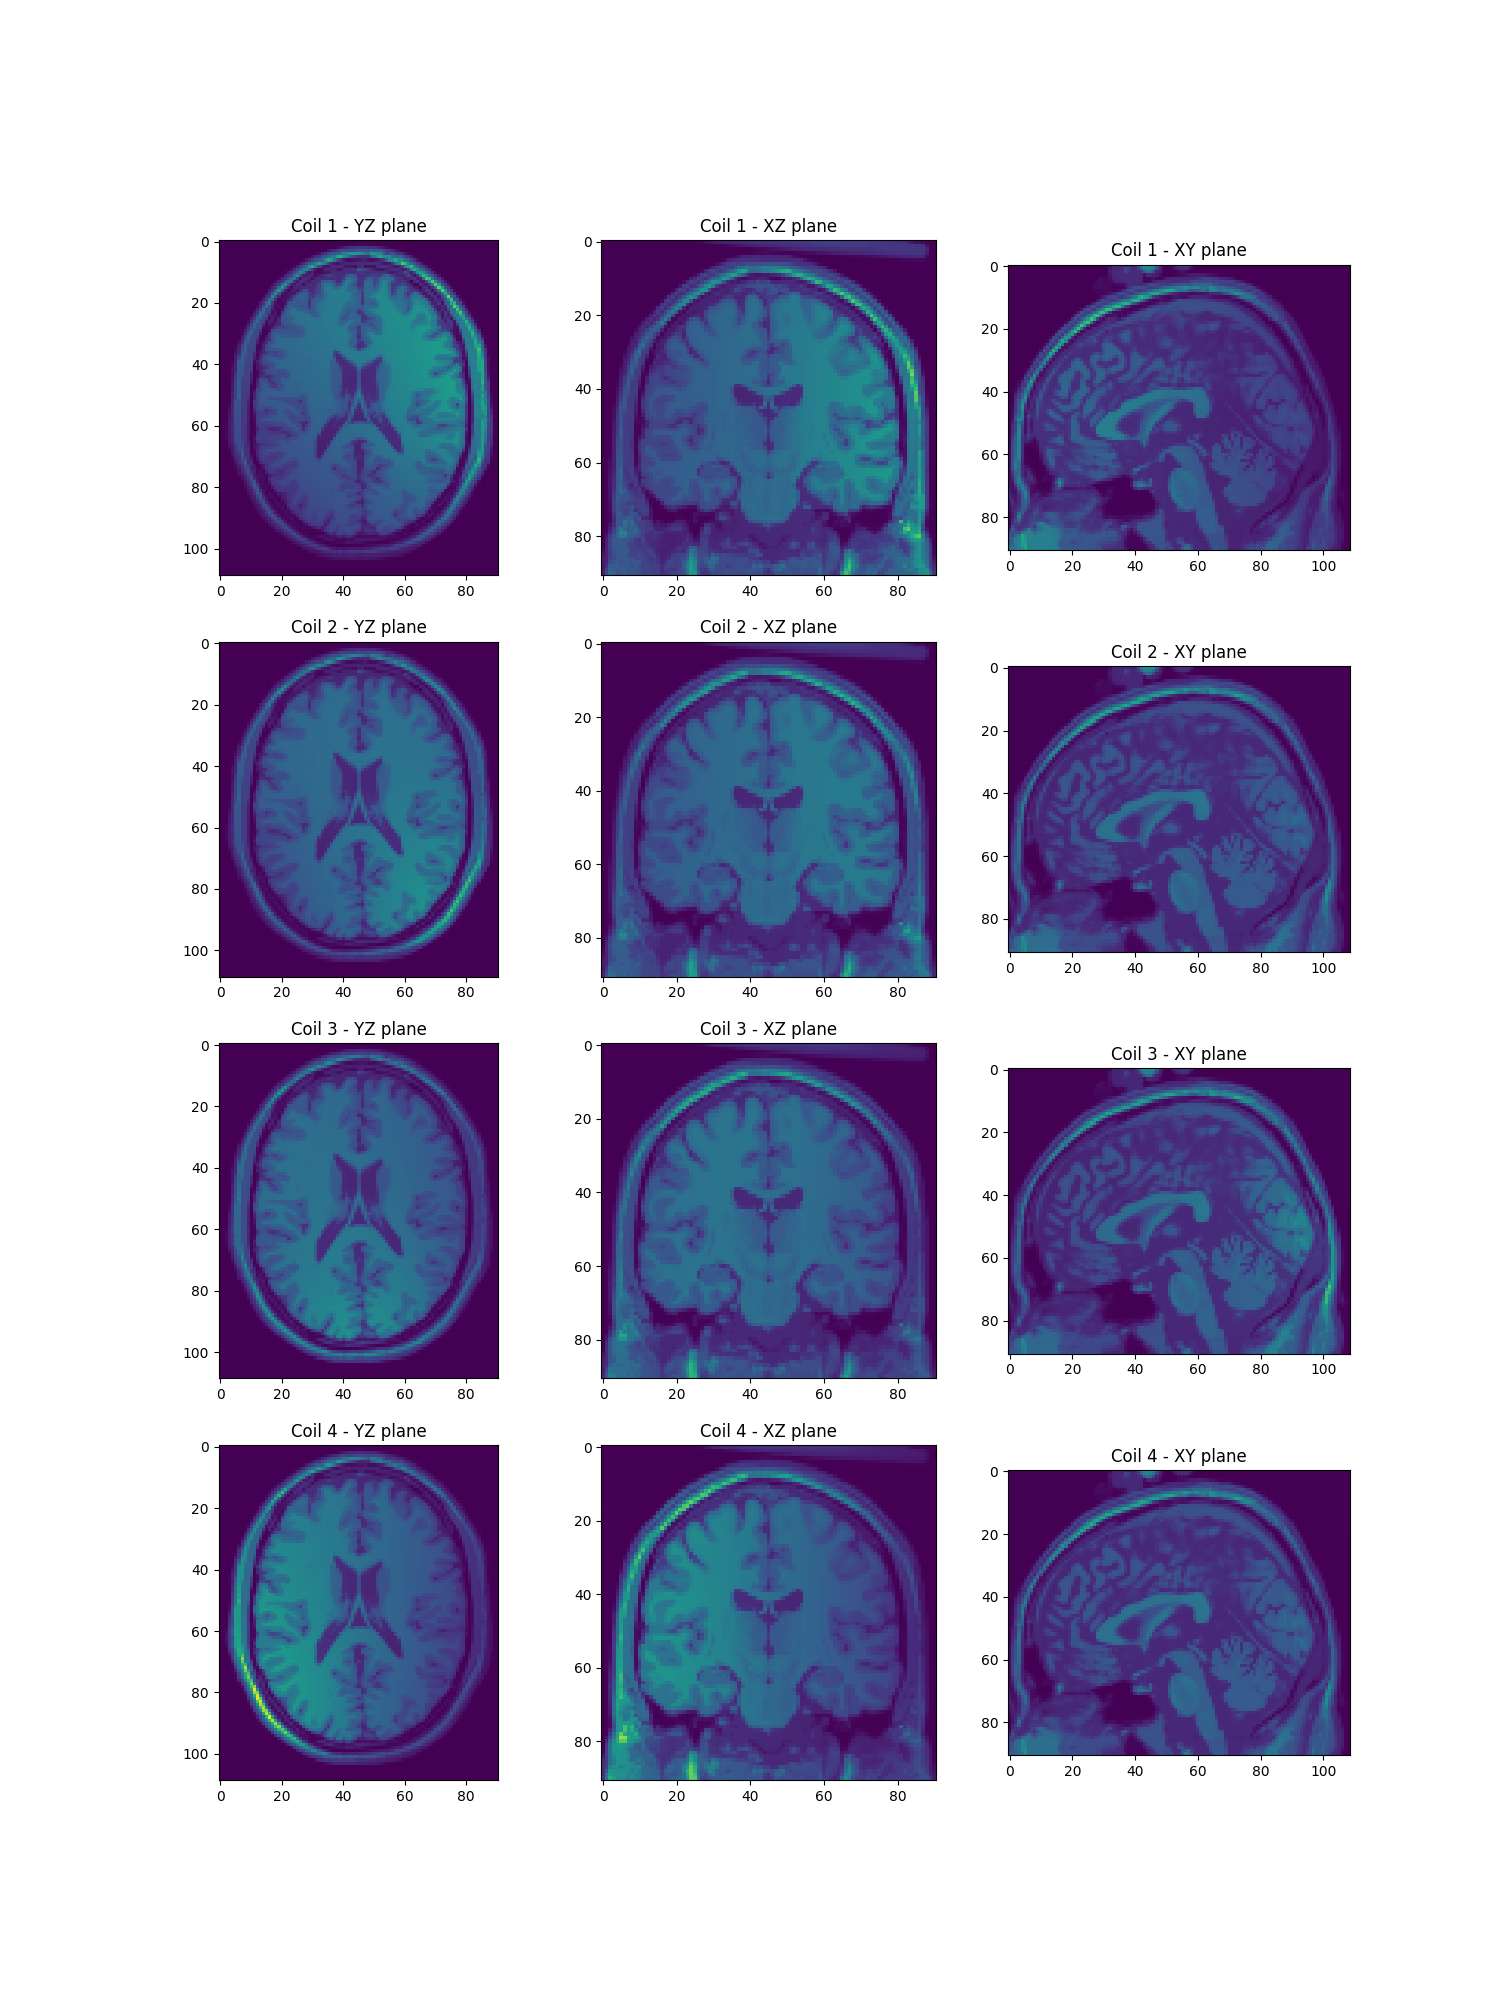

def show_maps(imgs):

"""Display 4D sensitivity maps in a 4x3 figure layout."""

n_coils, nx, ny, nz = imgs.shape

fig, axes = plt.subplots(4, 3, figsize=(15, 20))

imgs = np.abs(imgs)

for i in range(n_coils):

axes[i, 0].imshow(imgs[i, nx // 2, :, :], vmax=imgs.max(), vmin=imgs.min())

axes[i, 1].imshow(imgs[i, :, ny // 2, :], vmax=imgs.max(), vmin=imgs.min())

axes[i, 2].imshow(imgs[i, :, :, nz // 2], vmax=imgs.max(), vmin=imgs.min())

axes[i, 0].set_title(f"Coil {i+1} - YZ plane")

axes[i, 1].set_title(f"Coil {i+1} - XZ plane")

axes[i, 2].set_title(f"Coil {i+1} - XY plane")

plt.show()

Show the sensitivity maps

show_maps(actual_smaps)

<Figure size 1500x2000 with 12 Axes>

Show the per channel images

per_ch_mri = mri[None, ...] * actual_smaps # Generate per-coil MRI data

show_maps(per_ch_mri)